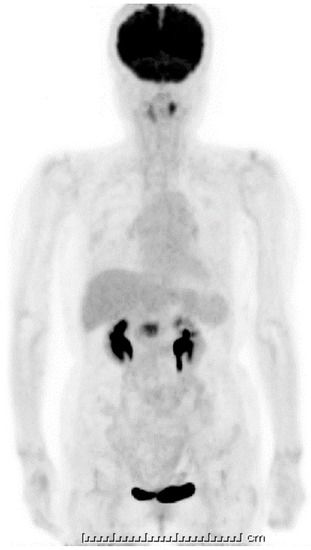

Figure 5.

18F-fluorodeoxyglucose positron emission tomography (FDG-PET). A strong uptake of FDG was visible at the pancreas head (SUVmax: 6.95); however, this looked smaller when compared with the initial computed tomography (CT) image. The one unit of under bar is indicating 1cm and total bar length is 25 cm.

Ten days after FNAB, positron emission tomography showed abnormal 18F-fluorodeoxyglucose uptake (SUVmax: 6.95); however, the pancreatic lesion seemed to have shrunk to 2.5 cm in size (Figure 5). Magnetic resonance imaging (MRI) demonstrated an obviously minimized tumorous lesion at the pancreas head (Figure 6). The mass lesion was visible as an iso-intensity signal in a T1-weighted image and as a faintly low-intensity signal in a T2-weighted image, while it was ill enhanced in an EOB image and the signal was heterogeneously repressed in a diffusion-weighted image. A subsequent CT, conducted one month after the FNAB, revealed further minimization of the pancreatic mass (Figure 1c,d). The images obtained in the next two months showed that the tumor had almost vanished. The tumor was no longer visible at the sixth month. During the post-diagnosis course, no medication was administered other than regularly taken hypotensive drugs. A written informed consent was obtained from the patient.